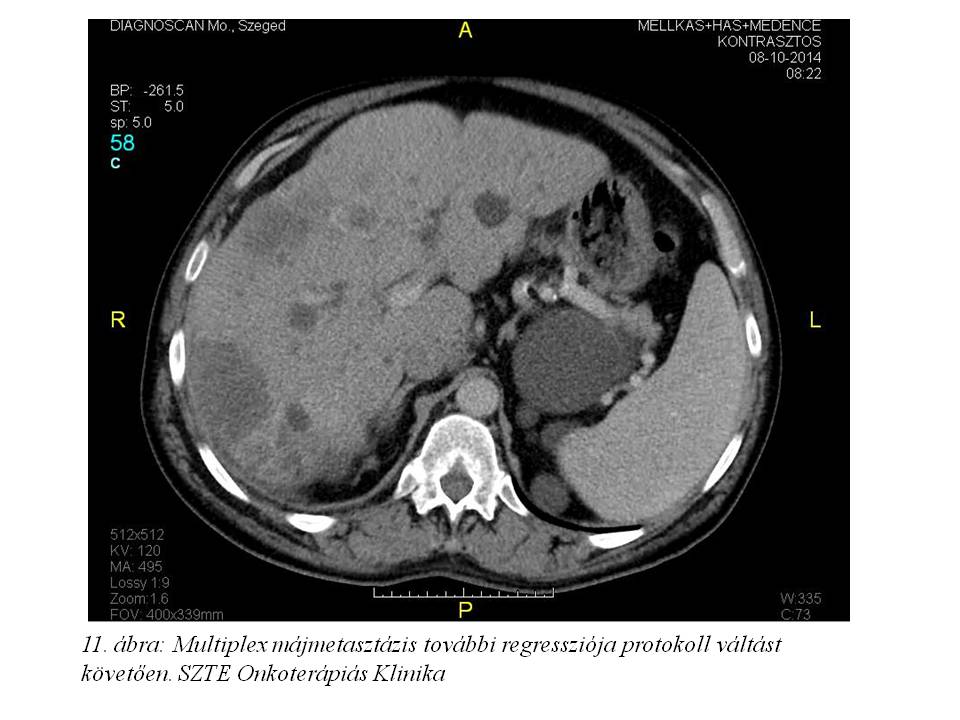

A fentiek értelmében a 16. ciklustól az oxaliplatin adásától eltekintettünk, kezelését DeGramont protokoll (Leucovorin + 5FU bolus + 5FU folyamatos infúzióban) szerint folytattuk. 2014. december 29-ig összesen 11 ciklust kapott. Az ez idő alatt elvégzett re-staging has-kismedence CT további regressziót írt le (2014.08.08. 10. ábra, 2014.10.08. 11. ábra, 2014.12.04. 12. ábra), a mellkas CT-n tüdőmetasztázis továbbra sem detektálható, a tumormarkerek tovább csökkentek (CEA: 0,8 ng/ml, CA 19-9: 7,32 U/ml), májfunkciós enzimek értéke normális.